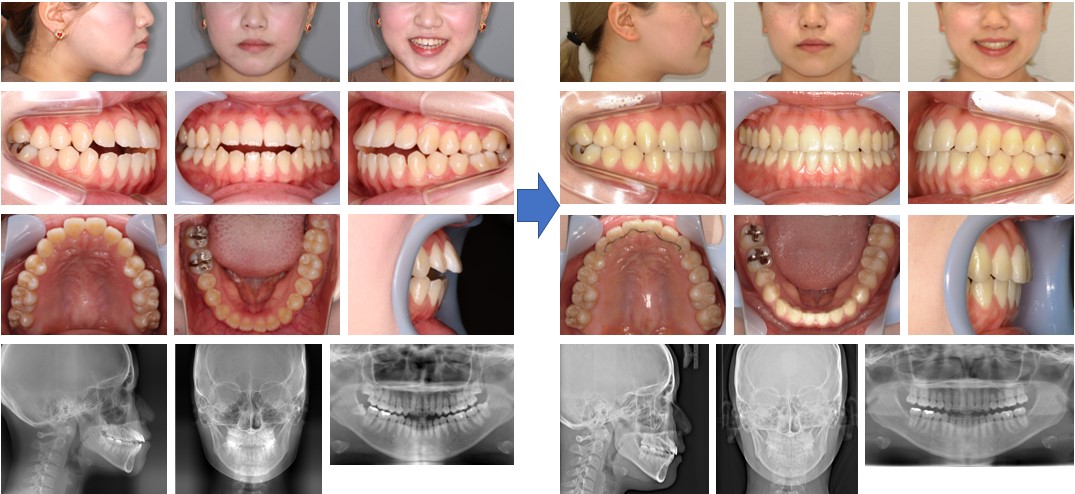

【治療例】初診時年齢:22歳4か月 / 性別:女性 / 主訴:前歯で咬めない、奥歯の負担が大きい、発音しにくい

症例の概要:幼少期に近隣の一般歯科で取り外し可能な装置で受け口の治療をしたが、日に日に開咬を呈してきたという。前歯で咬みきれないこと、発音障害があること、奥歯の負担が大きく、たまに痛みがあることが主訴であったが、舌癖や顔面正中線に対しての下顎骨の左方偏位も認められた。この症例は、マウスピース型(アライナー型)矯正装置(インビザライン®)と顎間ゴムのみで治療し、顔貌も改善した開咬症例である。

主訴: 前歯で咬めない、奥歯の負担が大きい、発音しにくい

診断名: 舌癖と下顎骨の左方偏位を認めた開咬症例

使用した主な装置: マウスピース型(アライナー型)矯正装置(インビザライン®)、顎間ゴム

抜歯/非抜歯および抜歯部位: 非抜歯(IPR)

※上記価格は税込価格です。消費税は10%で表示しております。

※こちらの症例は2020年7月から2024年6月に行った矯正です(現在も経過観察中)

治療期間:3年11か月

治療回数:36回

リスクの副作用:歯の移動や抜歯による違和感や疼痛、口内炎、歯肉退縮、歯根吸収が生じることがある